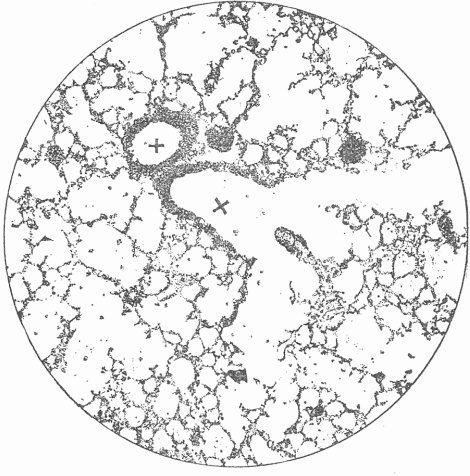

Fig. 6—Photograph Of A Section Of The Lung Of A Mouse. x x are the air tubes or bronchi which communicate with all of the small spaces. On the walls of the partitions there is a close network of blood vessels which are separated from the air in the spaces by a thin membrane.

The external surface passes into the interior of the body forming two surfaces, one of which, the intestinal canal, communicates in two places, at the mouth and anus, with the external surface; and the other, the genito-urinary surface, which communicates with the external surface at one place only. The surface of the intestinal canal is much greater in extent than the surface on the exterior, and finds enormous extensions in the lungs and in the great glands such as the liver and pancreas, which communicate with it by means of their ducts. The extent of surface within the lungs is estimated at ninety-eight square yards, which is due to the extensive infoldings of the surface [Fig 6], just as a large surface of thin cloth can, by folding, be compressed into a small space. The intestinal canal from the mouth to the anus is thirty feet long, the circumference varies greatly, but an average circumference of three inches may safely be assumed, which would give between seven and eight square feet of surface, this being many times multiplied by adding the surfaces of the glands which are connected with it. A diagram of the microscopic structure of the intestinal wall shows how little appreciation of the extent of surface the examination with the naked eye gives [Fig. 7]. By means of the intestinal canal food or substances necessary to provide the energy which the living tissue transforms are introduced. This food is liquefied and so altered by the action of the various fluids formed in the glands of the intestine and poured out on the surface, that it can pass into the interior of the body and become available for the living cells. Various food residues representing either excess of material or material incapable of digestion remain in the intestine, and after undergoing various changes, putrefactive in character, pass from the anus as feces.

By means of the lungs, which represent a part of the surface, the oxygen of the air, which is indispensable for the life of the cells, is taken into the body and carbonic acid removed. The interchange of gases is effected by the blood, which, enclosed in innumerable, small, thin-walled tubes, almost covers the surface, and comes in contact with the air within the lungs, taking from it oxygen and giving to it carbonic acid.